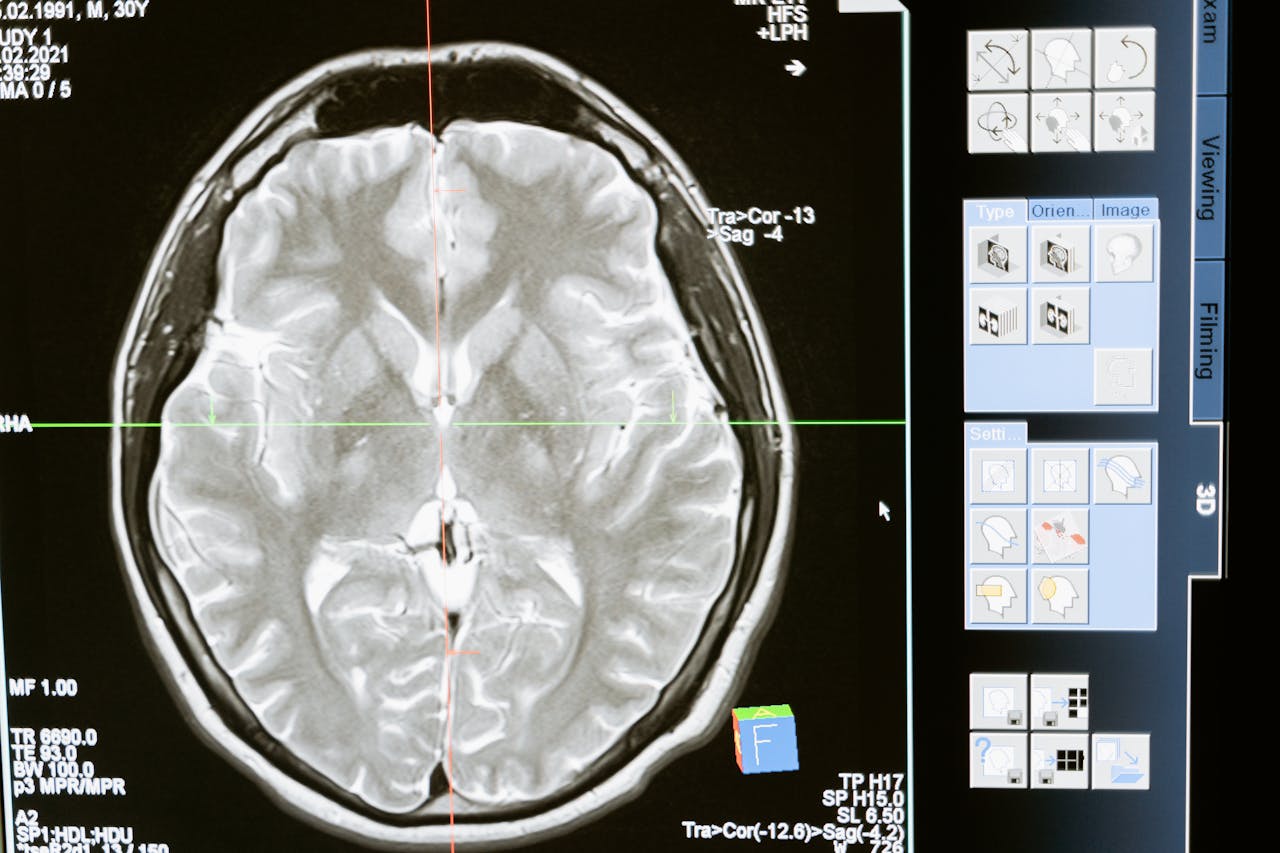

The human brain, a complex neural network influenced by genetics and environment, is studied through neuroimaging technologies like fMRI. Research links genetic variations to emotions and disorders, revealing neurotransmitter roles in mood regulation. Understanding these can improve cognitive health interventions, personalize treatments, and enhance resilience against cognitive decline and mental disorders.